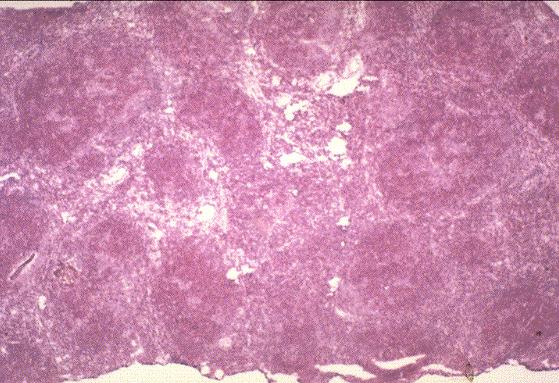

La enfermedad de Hodgkin es una entidad clínico-patológica que

se caracteriza por una población celular predominantemente reactiva que acompaña a las

células que verdaderamente constituyen el tumor.

Los estudios inmunohistoquímicos muestran una clara diferencia entre

el subtipo predominio linfocítico y el resto de subtipos, que constituyen lo que se

conoce como "formas clásicas" de enfermedad de Hodgkin. El reconocimiento del

linfoma anaplásico de células grandes como una entidad clínico-patológica ha hecho

desaparecer prácticamente el subtipo deplección linfocítica de enfermedad de Hodgkin.